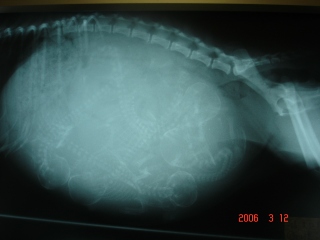

2年前の2006年3月12日は、うたちゃんのレントゲン撮りに行った日

その時に5babyおるのん知って驚いたわぁ(●´艸`)ムフフ.。oO

これがレントゲン写真

5つの骨見える~

それから2日後14日になみしず誕生してん

3月14日…2才になりまぁ~す